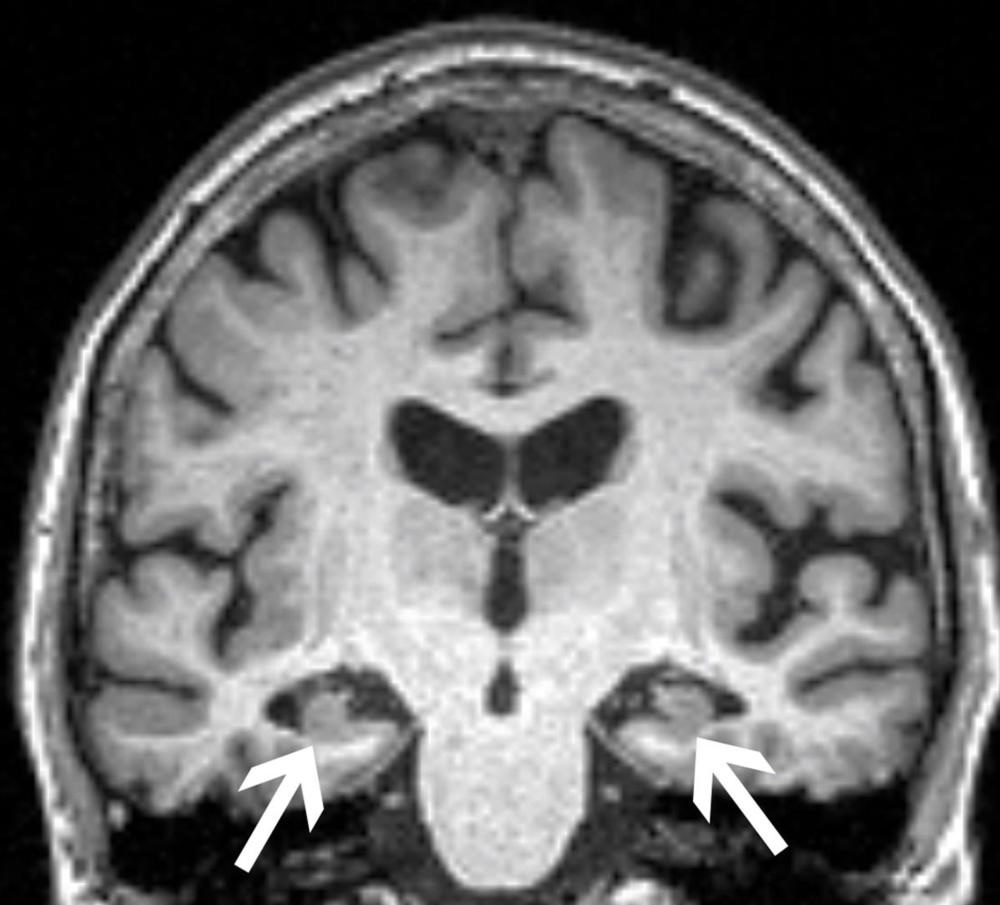

Diffusion-tensor (DTI)-MRI reveals how Alzheimer's -- and cerebral small vessel disease (cSVD) -- affect the brain's white matter microstructure, researchers have found.

"While physiological changes in white matter microstructural integrity can be observed in healthy aging, neurodegeneration due to Alzheimer's disease [AD] and cerebral small vessel disease are characterized by accelerated myelin disruption and axonal damage and loss," the group noted.

- While limbic tracts were mainly impacted by Alzheimer's disease pathology and the presence of APOE-ε4, "commissural, associative, and projection tract integrity" was more related to cSVD burden and cardiovascular risk, the group reported.